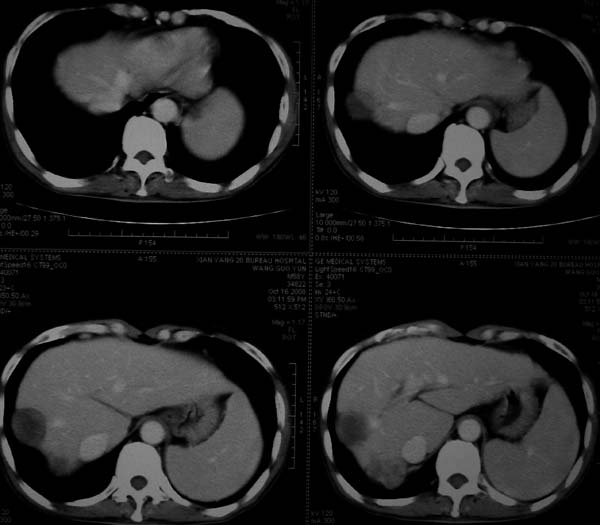

标题: CT16292:男,53岁,上腹部不适2月,B超发现肝内占位病变。 [打印本页]

标题: CT16292:男,53岁,上腹部不适2月,B超发现肝内占位病变。

象肝囊肿,有点黑,看不太清

符合肝ca增强,\"快进快出\";肝叶比例失常,右叶萎缩,肝裂增宽,脾大,肝硬化可能.

血管瘤,胆囊异位(图象很不清楚)。增强效果非常好,借鉴下!

肝脏体积变小,肝裂增宽,分布异常,肝尾叶增大,脾肿大,考虑肝硬化可能性大,右肝病灶呈现早期充盈,延迟强化考虑肝内胆管细胞癌可能,不除外血管瘤

肝硬化,多结节肝癌。比较典型的表现了。

肝叶比例失调,左叶增大,肝裂增宽,脾脏增大,门脉增宽,肝右叶包膜下多发结节样阴影,增强虽说强化幅度不大,但还是符合快进快出特点;考虑肝硬化、脾大、结节型肝癌。胆管细胞癌多有延时强化、肝包膜凹陷征、周围胆管扩张等特点,本例明显不符;故不考虑。